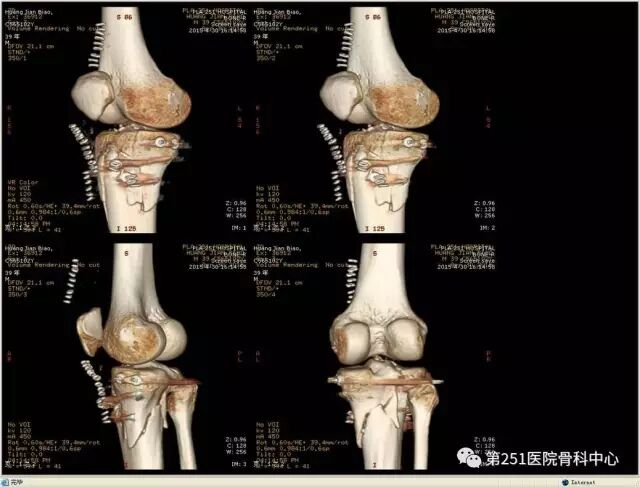

病例6:男性,39岁,车祸伤SchatzkerⅥ型胫骨平台骨折。

![]()